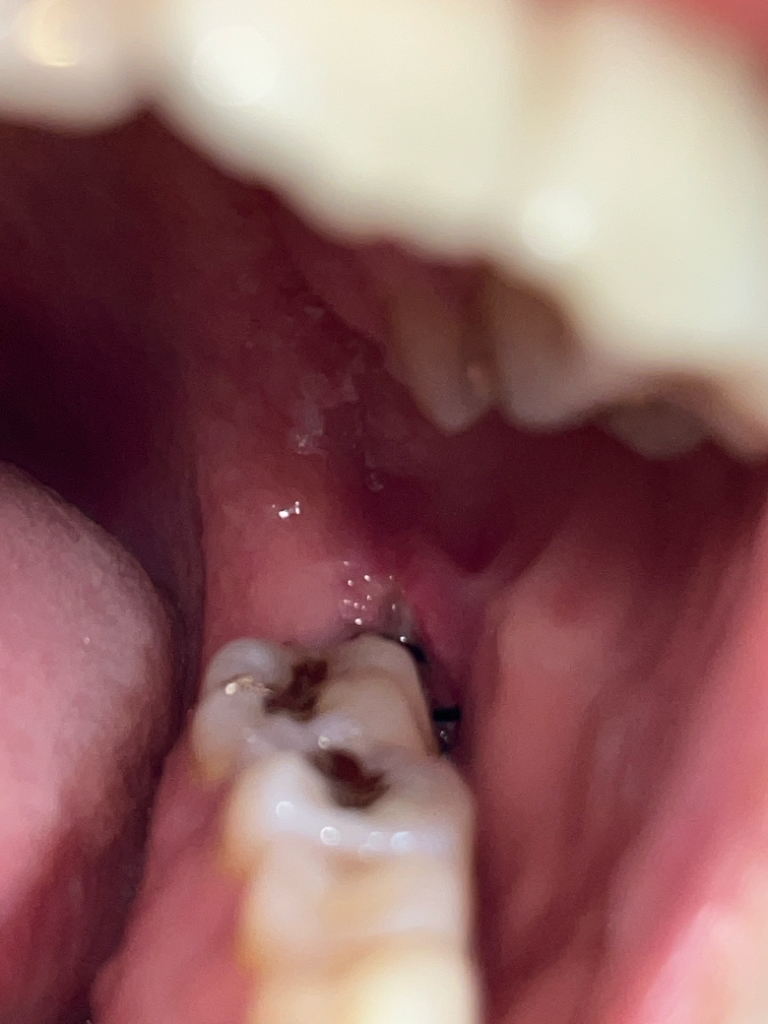

매복사랑니 발치 후 5일이 지났는데 통증이 아직 심해요. 드라이소켓인가요?

19일 오전 10시경에 왼쪽 아래 완전매복사랑니 발치를 했습니다. 발치 후 주의사항 전부 지켰고 처방해주신 약도 전부 다 복용한 상태입니다.

발치 후 5일 가량 지났는데 아직 밥 먹기도 힘들고 자려고 누우면 통증이 심해집니다.. 사진상 잘 안 보이지만 드라이소켓일 가능성이 있나요? 통증은 언제부터 완화될까요..?

• 1번 째 사진